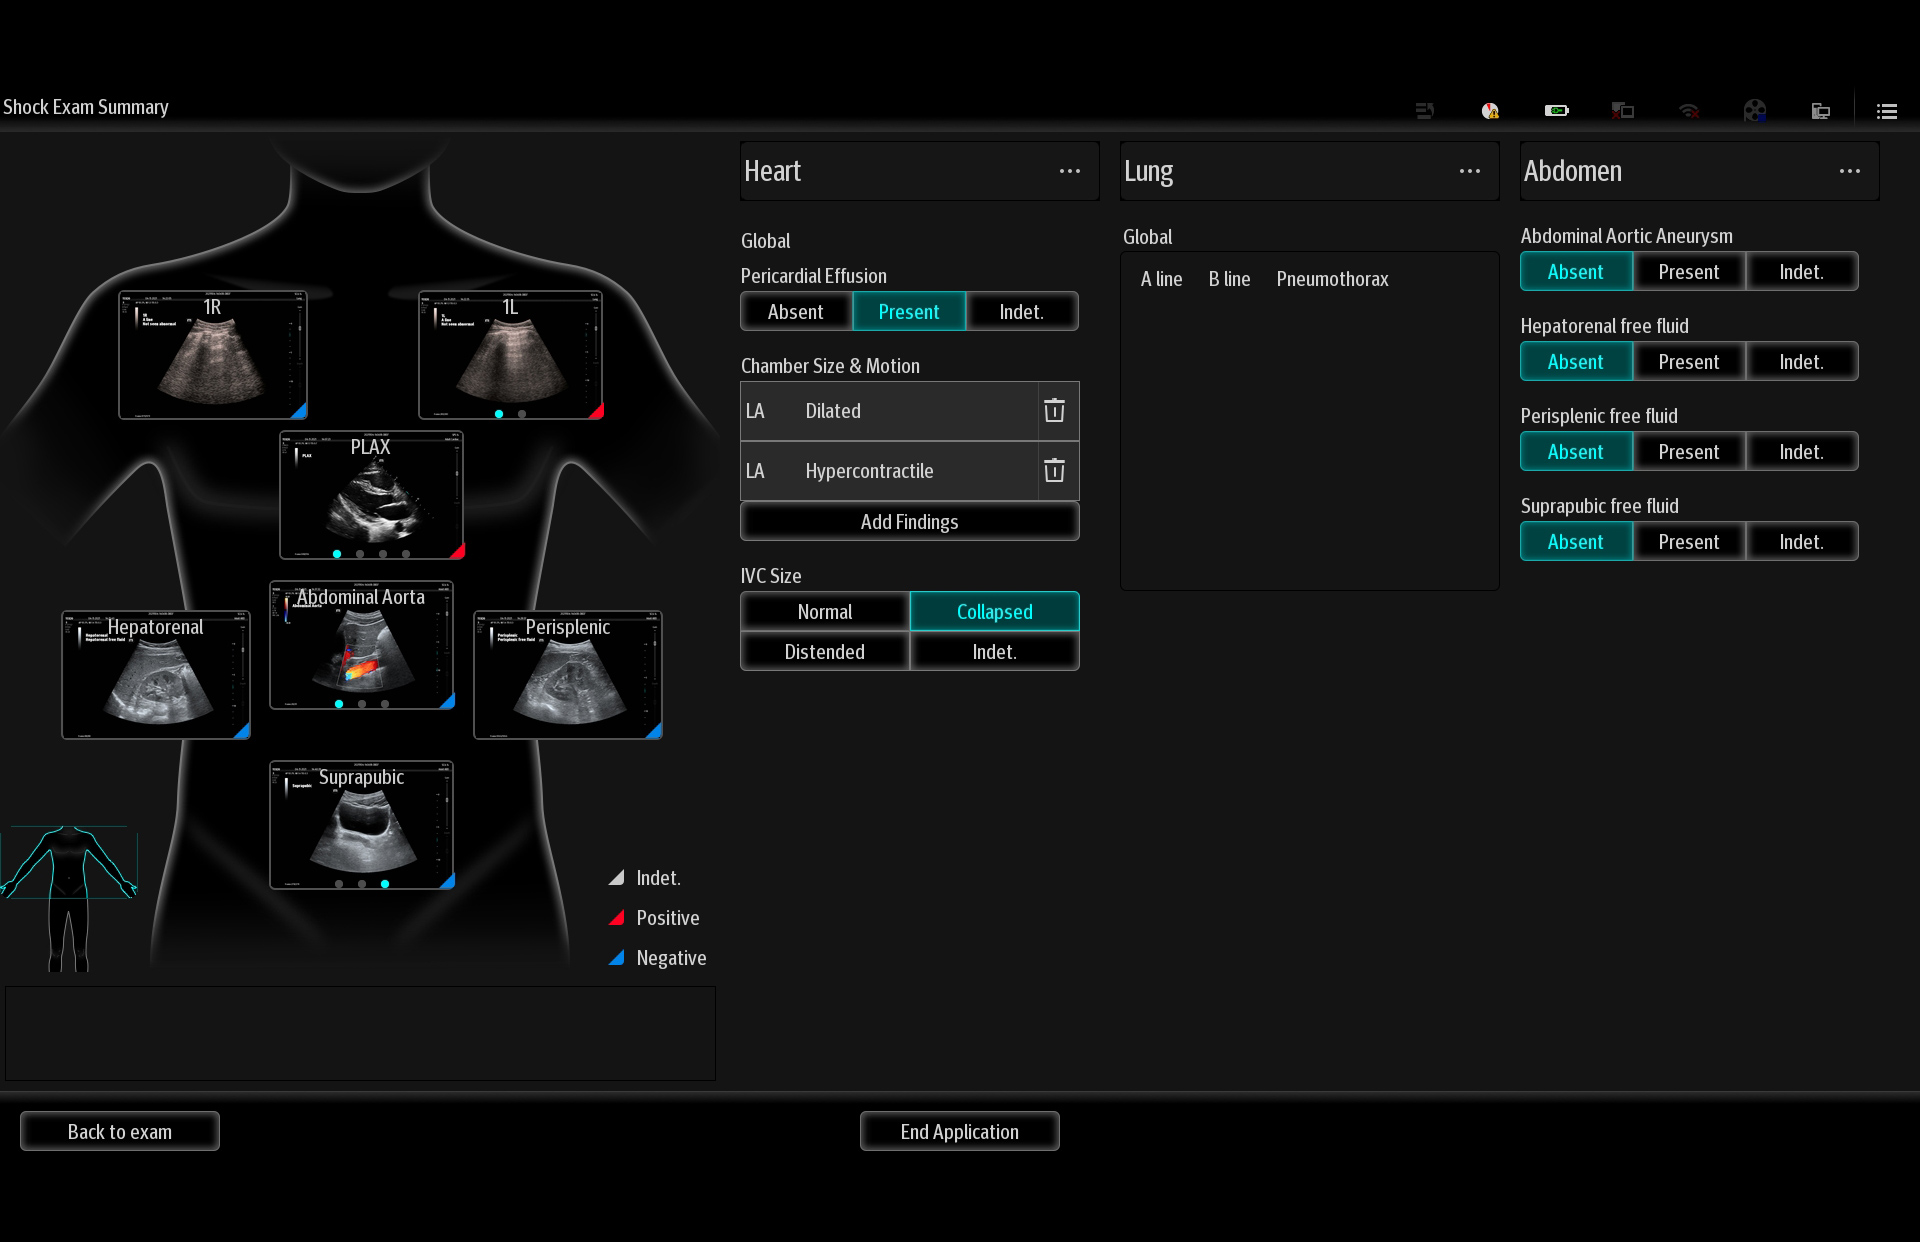

Mindray's Emergency Ultrasound Solutions address clinical challenges through a systemic approach. Those solutions cover the entire emergency care process from pre-hospital rescue and ambulance transport to ER treatment and in-hospital transfer. The versatility of Mindray Ultrasound shaping from Tablet system, Laptop-based system to Handheld Ultrasound system brings up the power of Ultrasound at the point of care. Clinical oriented smart features and protocols assist decisions with confidence.